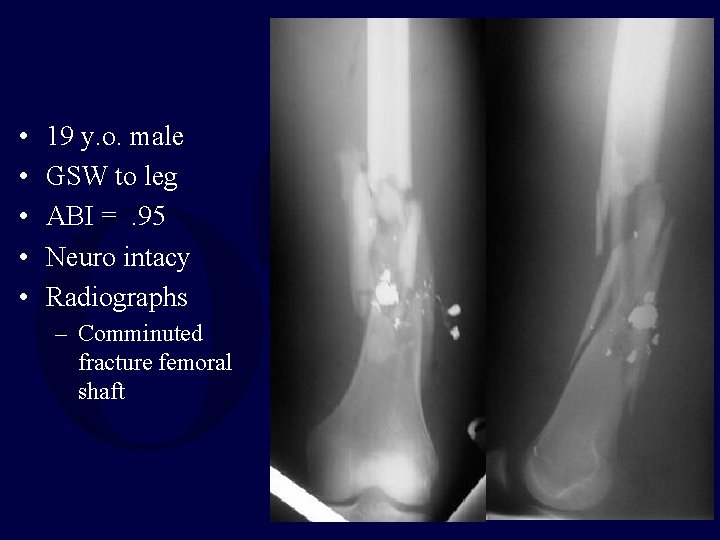

• • • 19 y. o. male GSW to leg ABI =. 95 Neuro intacy Radiographs – Comminuted fracture femoral shaft